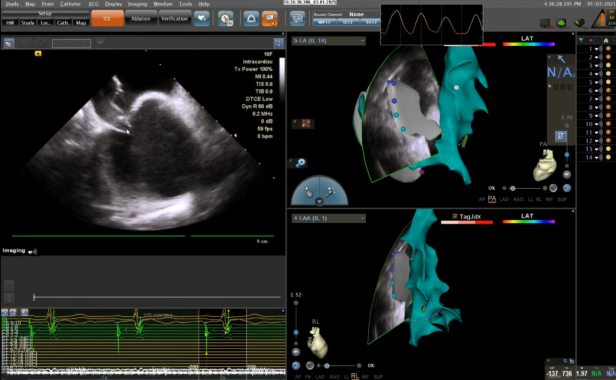

目前,房颤的主要治疗方式包括药物治疗和介入导管消融。其中,射频消融通过阻断异常电信号,已成为主流治疗方法。然而,传统手术需依赖X射线透视来辅助导管定位,存在一定辐射暴露,对孕妇、青少年等特殊人群不适用。我院近年来引进的“零射线”房颤射频消融术,称为绿色电生理技术,通过心腔内三维超声导管(ICE) 联合三维标测系统结合,实现全程无X射线的精准治疗,解决了特殊人群的手术问题。

心腔内三维超声导管(ICE)通过股静脉进入心腔,实时生成高分辨率心脏解剖图像,并同步整合至三维标测系统CARTO 3,构建动态三维心脏模型,术中实时跟踪导管位置,像在心脏里安装“GPS”一样,结合三维模型实现可视化消融,全程动态检测心包积液与血栓,减少并发症风险,这一过程无需依赖X射线,即可实现。